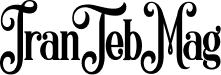

در حالت طبیعی، مفصل زانو با غضروف مفصلی پوشیده شده است؛ این بافت نرم و لغزنده مانند یک لایه محافظ عمل کرده و حرکت استخوانها را بدون اصطکاک و درد ممکن میکند. در آرتروز زانو، این غضروف بهتدریج دچار فرسایش میشود. با کاهش یا از بین رفتن غضروف، استخوانها مستقیماً روی هم ساییده میشوند که نتیجه آن درد، التهاب، خشکی مفصل و کاهش دامنه حرکتی است.

آرتروز زانو یا استئوآرتریت زانو (Knee Osteoarthritis) یک بیماری دژنراتیو (تحلیلبرنده) مفصل است که در آن غضروف مفصلی بهتدریج دچار فرسایش و تخریب میشود. غضروف یک بافت نرم، انعطافپذیر و لغزنده است که انتهای استخوانهای ران و ساق را در محل مفصل میپوشاند و مانند ضربهگیر، مانع ساییده شدن استخوانها به یکدیگر میشود.

در آرتروز، این غضروف به مرور زمان نازک شده یا کاملاً از بین میرود. نتیجه این فرایند، تماس مستقیم استخوانها، ایجاد اصطکاک، بروز التهاب، شکلگیری خارهای استخوانی (استئوفیت) و در نهایت درد و محدودیت حرکتی است.